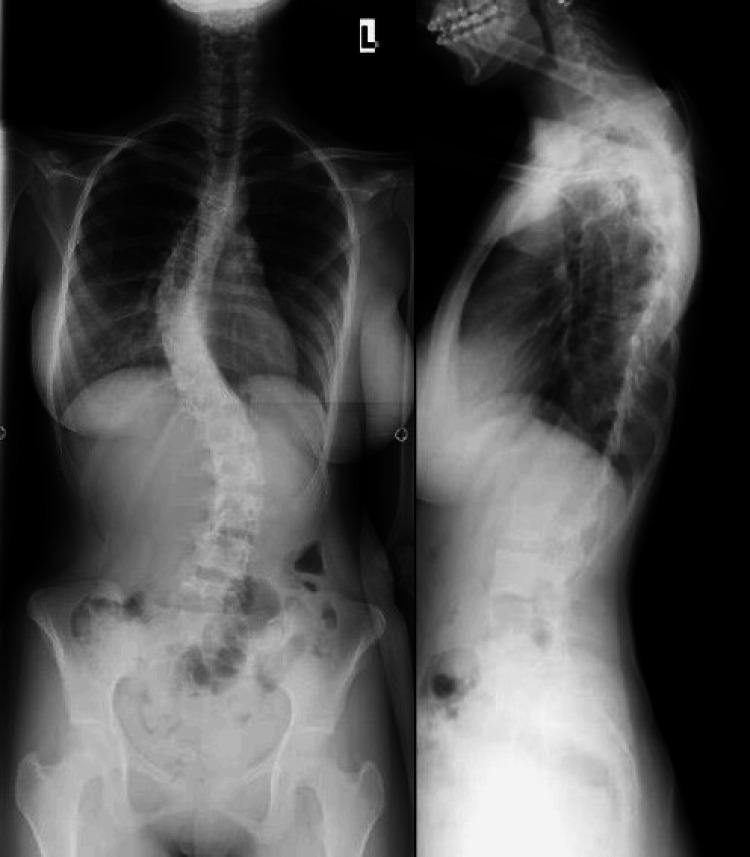

This case report presents the case of a 22-year-old female patient with a history of adolescent idiopathic scoliosis who underwent posterior spinal fusion and instrumentation from T4 to L5 at age 17. Her postoperative course was uneventful for five years, during which she remained asymptomatic and functionally independent. At age 22, she developed insidious axial low back pain without trauma or neurological symptoms. Imaging revealed a right L5 pedicle fracture with no evidence of implant loosening or pseudoarthrosis. Conservative management, including nonsteroidal anti-inflammatory drugs (NSAIDs), local injections, and physical therapy, failed to relieve symptoms. A CT scan confirmed solid fusion and an isolated pedicle fracture. Surgical removal of the instrumentation was performed, followed by application of a thoracolumbar orthosis. The patient returned to full daily activities without pain by one year postoperatively. This case highlights a rare complication of distal pedicle stress fracture after long-segment fusion, emphasizing the need for awareness of junctional stress-related pathology in long-term follow-up and the effectiveness of timely surgical management.

本病例报告介绍了一名22岁女性患者,该患者有青少年特发性脊柱侧弯病史,17岁时接受了从T4至L5的后路脊柱融合及内固定术。术后五年她的病程平稳,在此期间她没有症状,功能独立。22岁时,她在没有外伤或神经症状的情况下逐渐出现隐匿性轴向腰背痛。影像学检查显示L5右侧椎弓根骨折,没有植入物松动或假关节形成的迹象。包括非甾体类抗炎药(NSAIDs)、局部注射和物理治疗在内的保守治疗未能缓解症状。CT扫描证实融合良好且为孤立性椎弓根骨折。遂进行了内固定器械的手术取出,随后应用了胸腰骶矫形器。术后一年,患者恢复了全部日常活动且无疼痛。本病例突出了长节段融合后远端椎弓根应力性骨折这一罕见并发症,强调了在长期随访中需要关注交界区应力相关病变以及及时手术治疗的有效性。